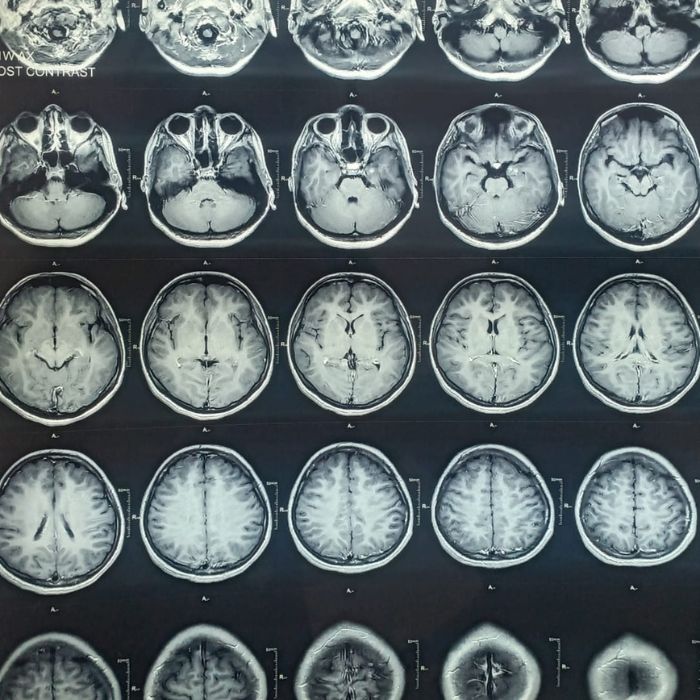

Tumor

Tumor begins when healthy cells in the brain or spinal cord change and grow out of control, forming a mass. A cancerous tumor spreads to other parts causing damage along its path. When the tumor is restricted to one location without causing significant damage it is said to be benign. The symptoms can be recurrent headaches, persistent vomiting, seizures, visual or hearing issues or even paralysis. Tumors are detected generally by imaging studies like MRI and CT scan. Further tests may be required to confirm the type, extent and to know if other body parts are involved. Treatment can be challenging at times and may require either medication, surgery, radiation or a combination.